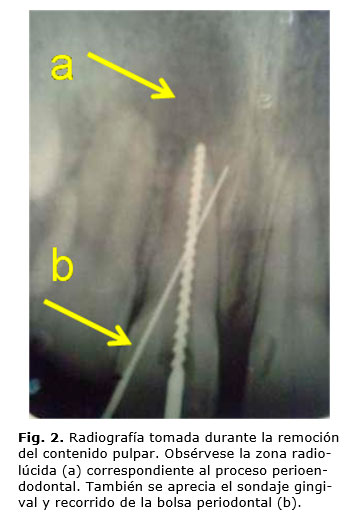

Al sondaje periodontal se detecta presencia de bolsa de 7 mm mesial del incisivo central maxilar izquierdo. Al examen radiográfico se detecta la presencia de un proceso crónico a nivel del tercio apical de la raíz del incisivo central que involucra parte del tercio apical de la raíz de incisivo lateral del mismo lado (fig. 2).

El examen extrabucal no arrojó datos significativos y las pruebas de vitalidad eléctrica y térmica resultaron negativas en el incisivo central y positivas en el lateral. Por lo cual se llegó al diagnóstico de LEP-LPS en el incisivo central y LPP en el lateral.